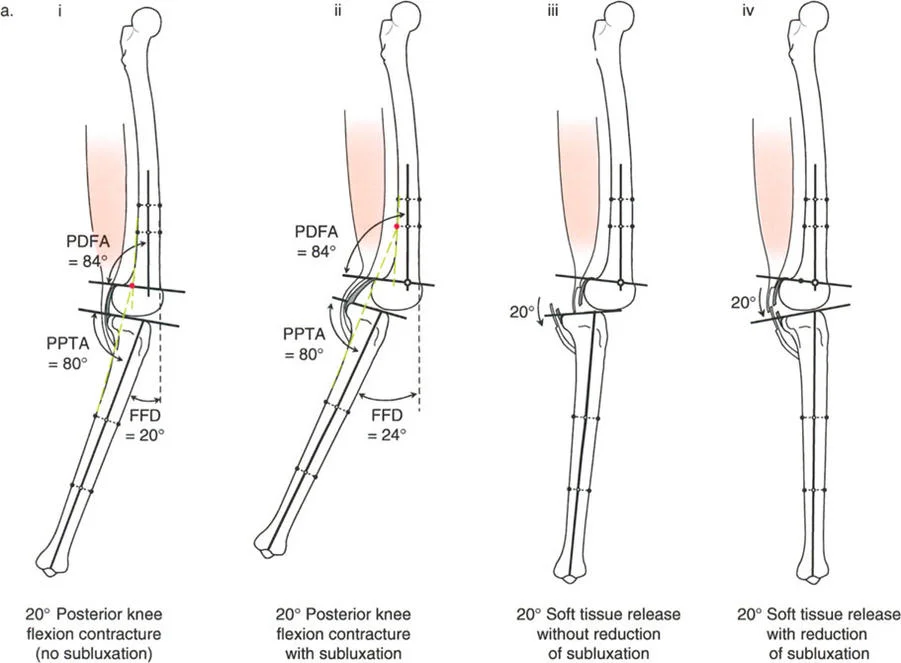

- تحدُّد حركة الركبة (Flexion Deformity - FFD): عدم القدرة على مد الركبة بالكامل، بحيث تظل الركبة في وضعية انثناء جزئي حتى عند محاولة فردها. يمكن أن يكون هذا ناتجًا عن تشوهات عظمية (مثل تقوس عظم الفخذ أو الساق للأمام) أو تقلصات في الأنسجة الرخوة (الأوتار والعضلات).

تصحيح تحدد حركة الركبة (Flexion Deformity - FFD)

تحدُّد حركة الركبة هو عدم القدرة على مد الركبة بالكامل. يمكن أن يكون سببه عظميًا أو ناتجًا عن تقلص في الأنسجة الرخوة.

- التشخيص الدقيق: يجب تحديد ما إذا كان تحدد الحركة ناتجًا عن تشوه عظمي (تقوس أمامي في الفخذ أو الساق) أو تقلص في الأنسجة الرخوة (الأوتار الخلفية، محفظة المفصل).

- قطع العظم التمديدي (Extension Osteotomy):

- إذا كان التشوه عظميًا، يتم إجراء قطع عظم تمديدي في عظم الفخذ أو الساق لتصحيح التقوس.

- الأستاذ الدكتور محمد هطيف يؤكد على أهمية عدم تصحيح الساق بأكثر من 90 درجة PPTA لتجنب فقدان الميل الخلفي الطبيعي للساق.

- تحرير الأنسجة الرخوة (Soft Tissue Release):

- إذا كان السبب هو تقلص الأنسجة الرخوة، فقد يتم إجراء إطالة للأوتار أو تحرير لمحفظة المفصل.

- إزالة النتوءات العظمية (Osteophyte Resection):

- إذا كانت النتوءات العظمية الأمامية تمنع المد الكامل، يمكن إزالتها جراحيًا.

- التصحيح التدريجي: في حالات تحدد الحركة الشديدة أو المعقدة، قد يكون التصحيح التدريجي باستخدام التثبيت الخارجي هو الخيار الأكثر أمانًا.